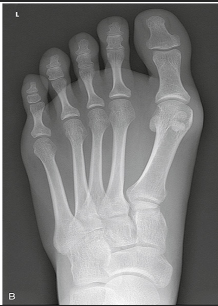

Name this projection.

AP oblique foot

Describe the position of the patient.

Seated or supine with their knee flexed and lower leg/foot rotated medially 30 degrees

Where does the CR enter?

Base of the 3rd metatarsal

What is demonstrated?

The lateral side of the foot from the toes to heel, the sinus tarsi, and the tuberosity of 5th metatarsal

The ________ metatarsals should be free of superimposition.

3rd-5th

Which metatarsals should be superimposed?

1st and 2nd

What could be done to demonstrate the opposite aspect of the foot?

Rotate the foot out laterally 30 degrees